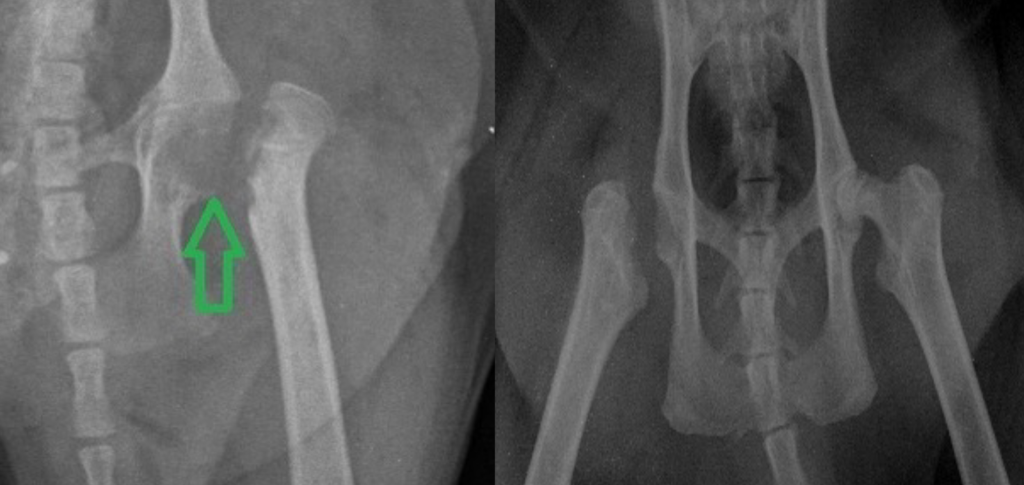

- Резекционная артропластика – удаление поврежденной головки бедра.

(из практики Максима Александровича Кардаша)